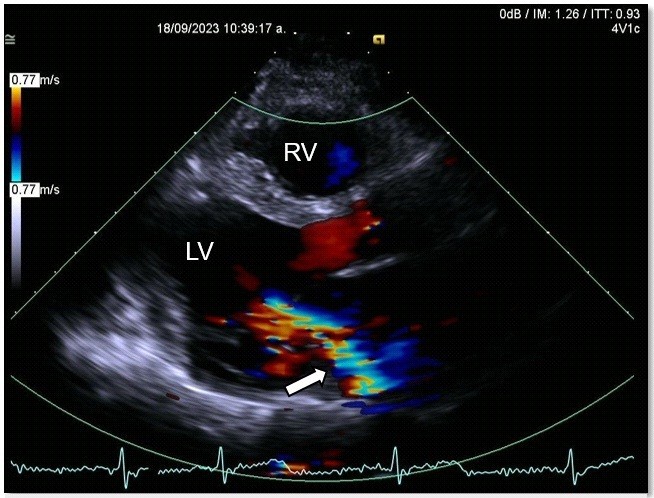

A transthoracic echocardiogram revealed dilated, possibly Chagas-related cardiomyopathy due to an aneurysm involving two segments (basal inferolateral and basal anterolateral), with an aneurysm-to-mouth width ratio of 0.45; the remaining mobility was normal. The LV had an enlarged diameter, eccentric hypertrophy and a 49% LVEF. The mechanism of severe MR was secondary to annular dysfunction due to the aneurysm, in addition mitral annulus dilation and asymmetric tenting of the posterior leaflet, resulted in a wide, eccentric, and complex jet with a Coanda effect. The probability of pulmonary hypertension was low, with a pulmonary artery systolic pressure of 32 mmHg (Fig. 6, 7).

Figure 7. Echocardiogram, parasternal long-axis view: left ventricular ejection fraction=49%, severe mitral regurgitation with large eccentric jet and Coanda effect (white arrow)